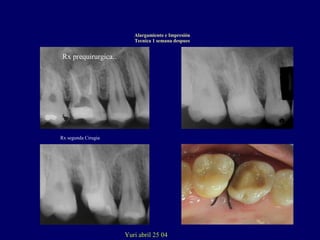

Rx segunda Cirugia

Rx primera cirugia.

Rx prequirurgica..

Yuri abril 25 04

Alargamiento e Impresión

Tecnica 1 semana despues